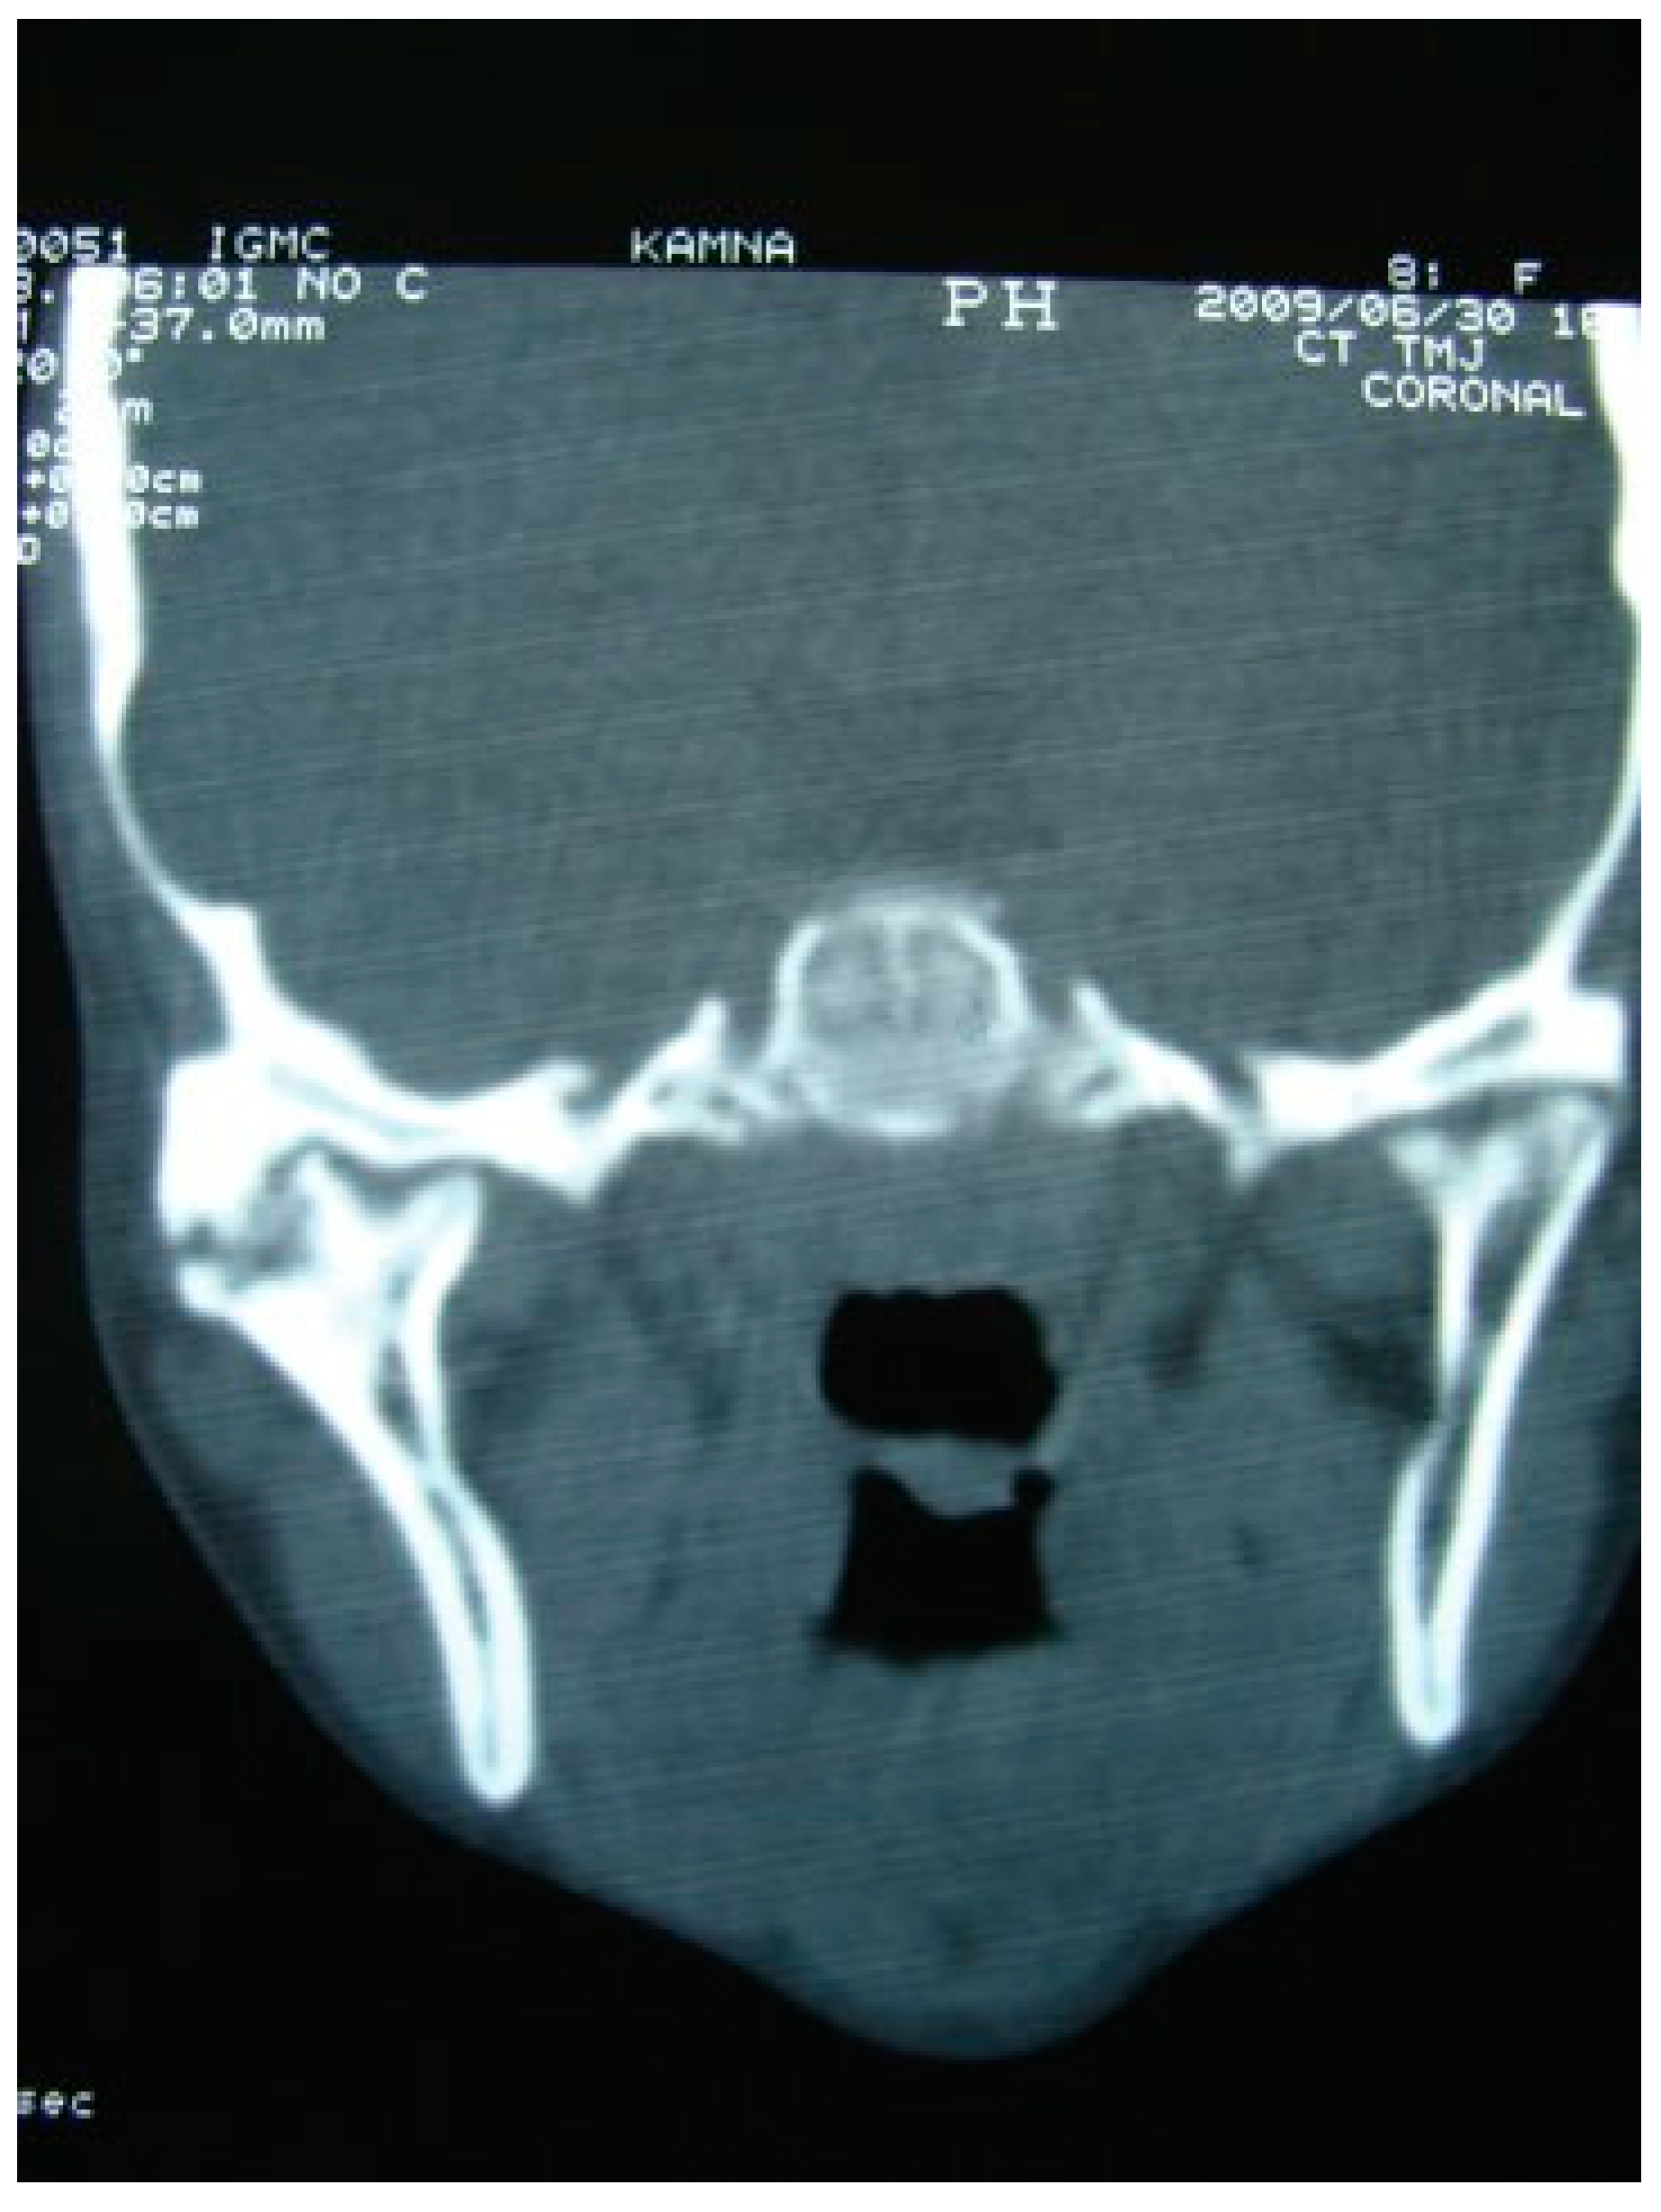

A retrospective study of post–ankylotic TMJ reconstruction of all the patients who underwent surgery for the TMJ ankylosis over a period of 11 years from 2002 to 2013, which were operated by the senior author (Y.B.), was undertaken to evaluate demographics, type of TMJ ankylosis, and modality of post–ankylotic TMJ reconstruction. The following inclusion criteria were considered for enrolling patients in this study: (1) history of traumatic injury to the face or jaws; (2) clinical and radiographic evidence of bony ankylosis at the time of presentation; (3) reconstruction of the TMJ using autogenous or alloplastic material after surgical release of ankylosis. Patients were assessed for (1) maximum interincisal opening pre and post operatively; (2) restored vertical ramal height; (3) occlusion; (4) facial symmetry; and (5) postoperative complications. Radiographic evaluation consisted of both preoperative and postoperative panoramic radiography Orthopentomogram (OPG) (Figure 1 and Figure 2) and CT scans in axial, coronal, and sagittal sections with three-dimensional reconstruction (Figure 3 and Figure 4). Surgical protocol was that the TMJ was approached through the Al-Kayat and Bramley’s incision and at least 2 to 2.5 cm resection of the ankylotic chunk was performed in all our cases. Ipsilateral and contralateral coronoidectomy was performed when required to achieve passive mouth opening. Interpositional arthroplasty was done using various materials such as temporalis fascia, temporalis muscle, and articular disc, whereas joint reconstruction was done using CCG and titanium reconstruction plate with condylar head. Intensive physiotherapy postoperatively was an integral part of protocol.

Figure 1. Preoperative OPG of right temporomandibular joint ankylosis.

Figure 3. Preoperative coronal CT scan of right temporomandibular joint ankylosis.